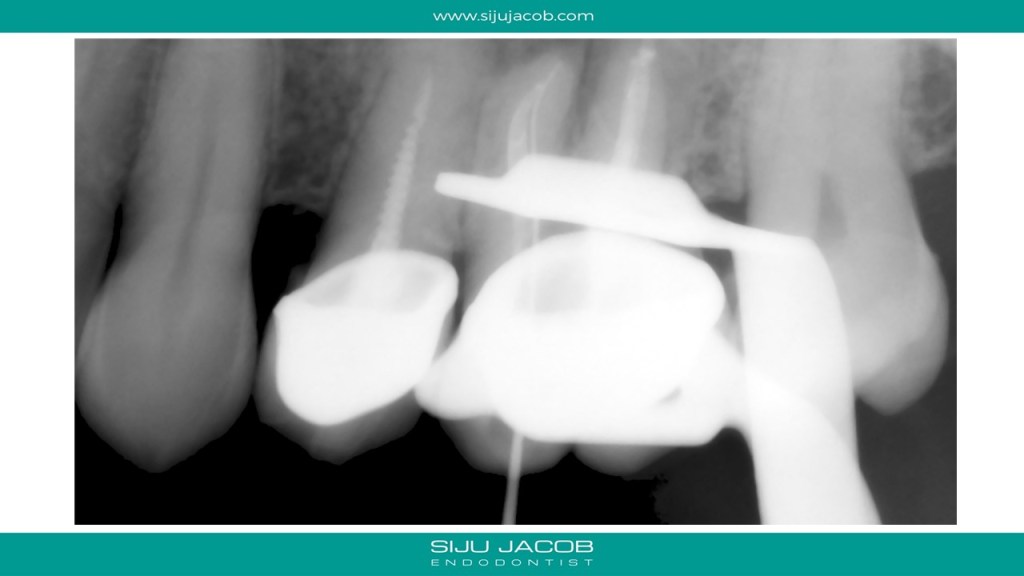

In the past, when we attempted Re-treatment, we used to re-treat all the canals. For the past 4-5 years, I’ve been doing mostly selective Re-treatment ie: treat only those roots or canals which need something to be done. Michael Trudeau calls it “Titrated Treatment”. Some of my friends on TDO call it “Image guided Treatment (IGT)”.

This is a Maxillary first molar treated several years ago and the patient came back with pain. CBCT shows missed MB2 with separate portal of exit. I located and treated only the MB2. Left the rest of the canals as they were.